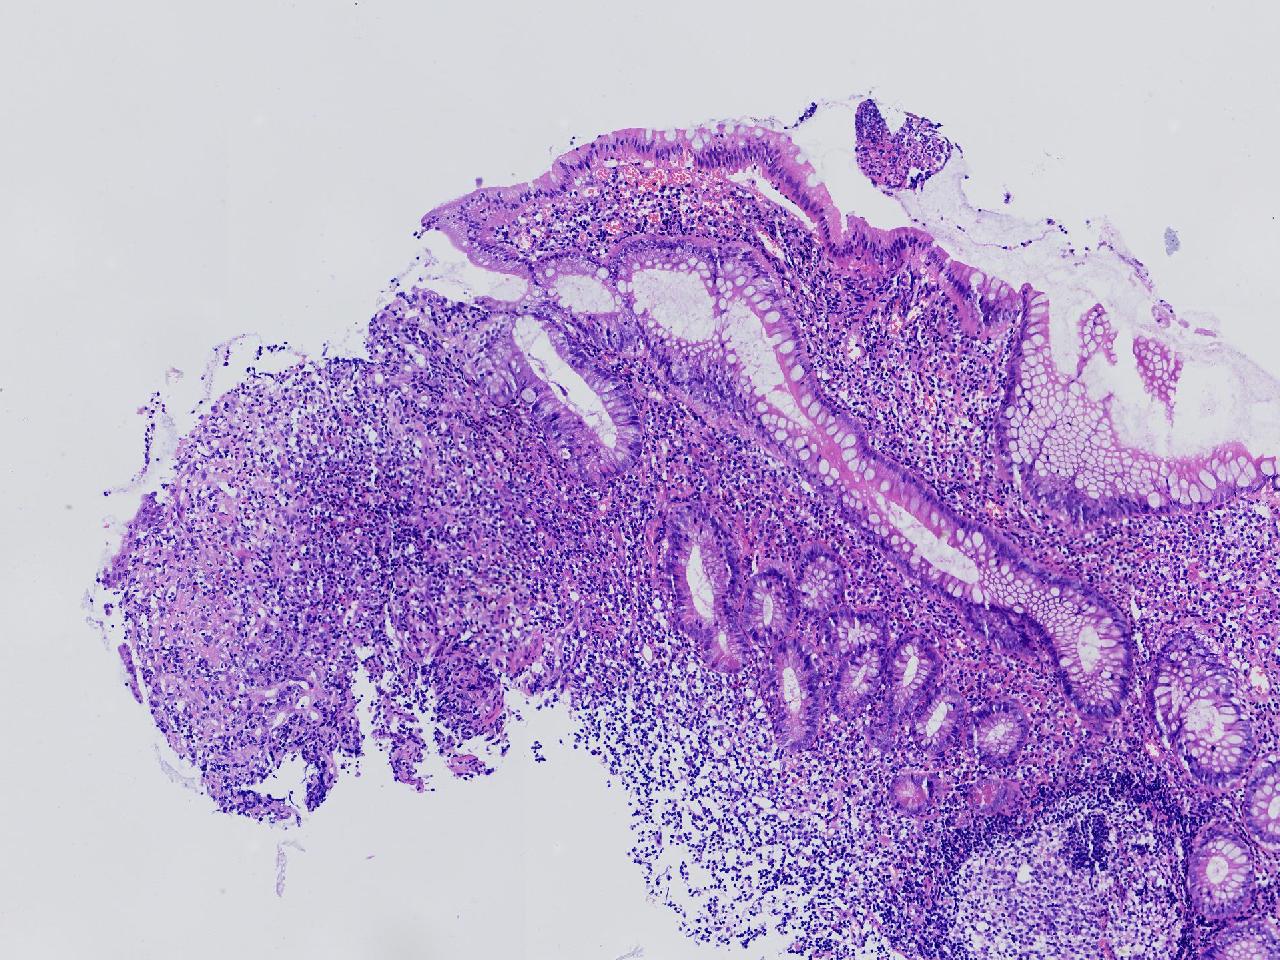

男,62岁,回盲部附近见多发片状溃疡,底覆薄白苔,周围粘膜充血水肿,活检2块,质软,弹性可。

回盲部活检

灰白色不整形软组织2块,直径均0.2厘米。

考虑:溃疡性结肠炎?

炎症性肠病要考虑,具体的类型不太好确定,需要结合临床。

上级医院会诊,不除外炎症性肠病,结合临床。